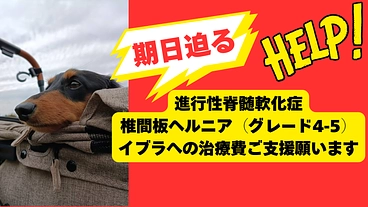

【進行性脊髄軟化症】2度大手術をしたイブラへ、治療費ご支援のお願い

- 現在

- 229,000円

- 支援者

- 35人

- 残り

- 13日